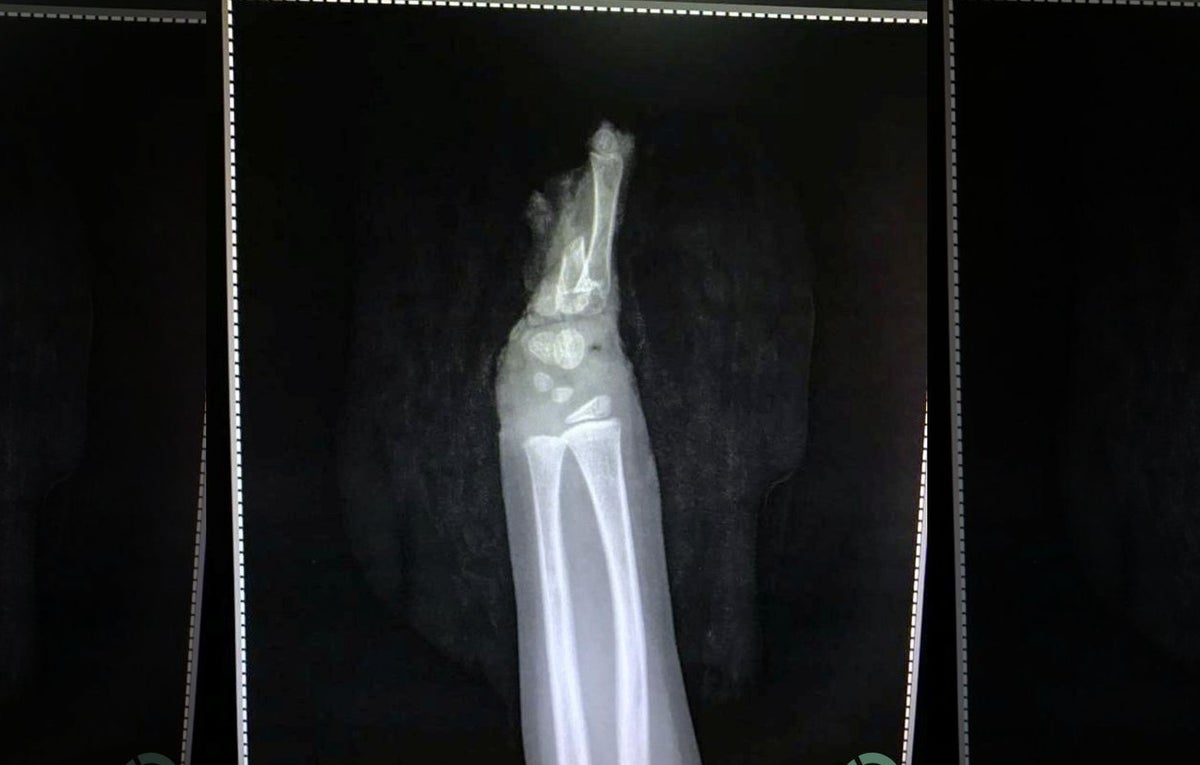

"Su mano izquierda estaba completamente cortada con parte de los huesos unidos al cuerpo mientras la piel y el músculo de dicha extremidad se desprendían", dijo el Dr. Abhishek Ghosha, un cirujano microvascular que trató al niño.

El menor fue sometido a una cirugía que duró seis horas, en la que los especialistas utilizaron injertos de piel y venas de una de las piernas del infante. “Al ver la corta edad del niño, se decidió intentar salvar la mano. El paciente fue llevado a cirugía inmediatamente después de llegar al hospital y se le administró anestesia", narró el galeno a los medios locales.

La mano amputada se observó de cerca bajo el microscopio y se notó un pequeño vaso sanguíneo dentro del músculo. Luego, este pequeño vaso se unió a la arteria principal del antebrazo con la ayuda de un largo injerto de vena tomado de la pierna”, continuó. "Comenzó la circulación de la mano y las venas se unieron minuciosamente".